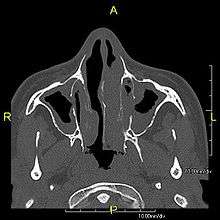

When accompanied by the combination of situs inversus (reversal of the internal organs), chronic sinusitis, and bronchiectasis, it is known as Kartagener syndrome (only 50% of primary ciliary dyskinesia cases include situs inversus).

The main consequence of impaired ciliary function is reduced or absent mucus clearance from the lungs, and susceptibility to chronic recurrent respiratory infections, including sinusitis, bronchitis, pneumonia, and otitis media. Progressive damage to the respiratory system is common, including progressive bronchiectasis beginning in early childhood, and sinus disease (sometimes becoming severe in adults). However, diagnosis is often missed early in life despite the characteristic signs and symptoms.[1] In males, immotility of sperm can lead to infertility, although conception remains possible through the use of in vitro fertilization and, as well as this, there have been reported cases where sperm were able to move.[2] Trials have also shown that there is a marked reduction in fertility in female sufferers of Kartagener's Syndrome due to dysfunction of the oviductal cilia.[3]

Many affected individuals experience hearing loss and show symptoms of glue ear which demonstrate variable responsiveness to the insertion of myringotomy tubes or grommets. Some patients have a poor sense of smell, which is believed to accompany high mucus production in the sinuses (although others report normal - or even acute - sensitivity to smell and taste). Clinical progression of the disease is variable with lung transplantation required in severe cases. Susceptibility to infections can be drastically reduced by an early diagnosis. Treatment with various chest physiotherapy techniques has been observed to reduce the incidence of lung infection and to slow the progression of bronchiectasis dramatically. Aggressive treatment of sinus disease beginning at an early age is believed to slow long-term sinus damage (although this has not yet been adequately documented). Aggressive measures to enhance clearance of mucus, prevent respiratory infections, and treat bacterial superinfections have been observed to slow lung-disease progression. Although the true incidence of the disease is unknown, it is estimated to be 1 in 32,000,[4] although the actual incidence may be as high as 1 in 15,000.